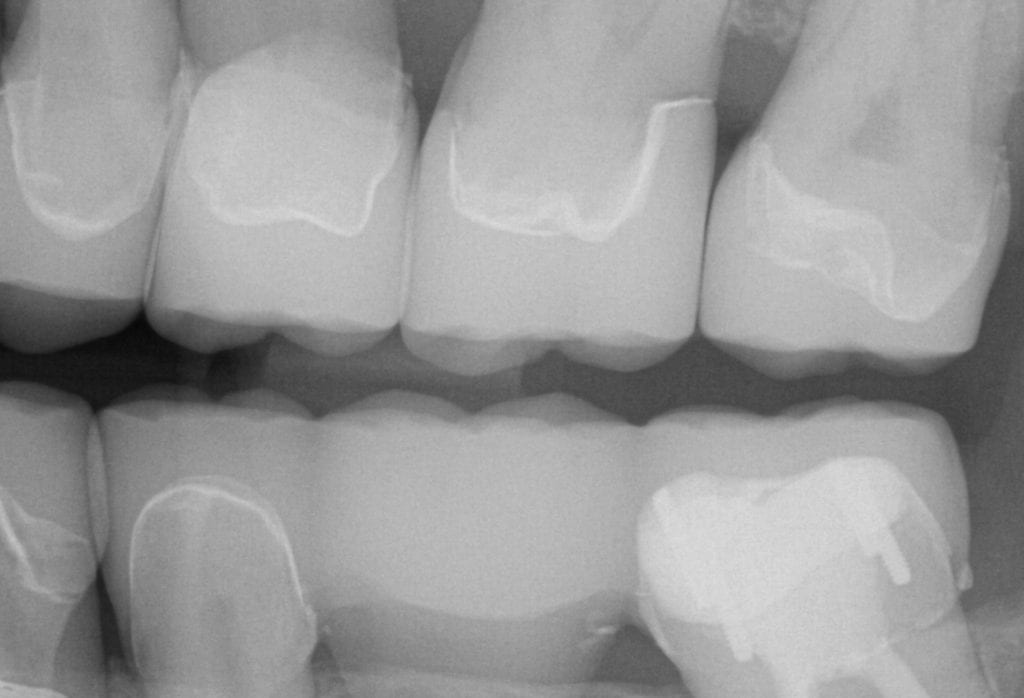

ONE WEEK POST-OP RADIOGRAPHS / CEMENT CHECK